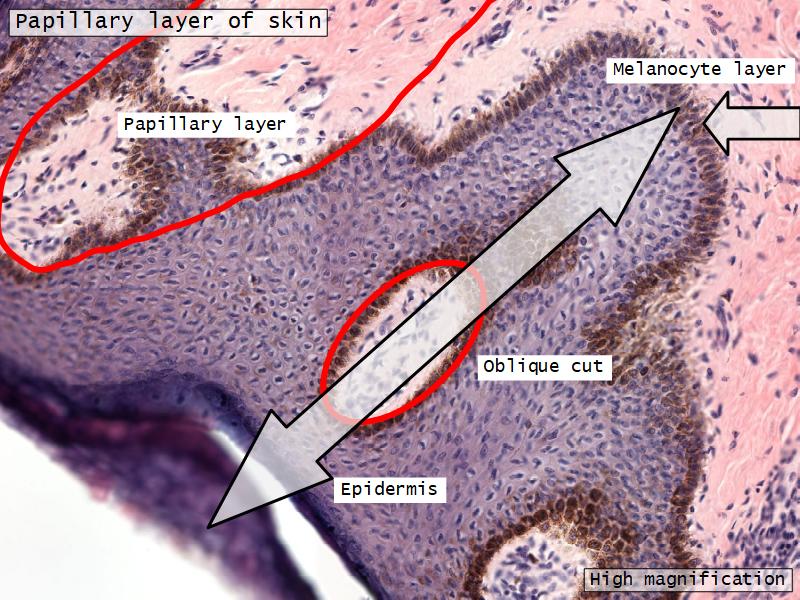

What are the main morphological features of the nipple?

(4)

Morphology

- Covered with skin

- Consists of dense collagenous connective tissue

- Interlaced with smooth muscle fibres

- Contains openings of lactiferous ducts

Skin

- Keratinized stratified squamous epithelium

- Sebaceous glands

Stroma

- Collagenous connective tissue

- Irregular dense connective tissue

- Smooth muscle

- Fibres and bundles

- Lactiferous sinusses

- Stratified cuboidal epithelium